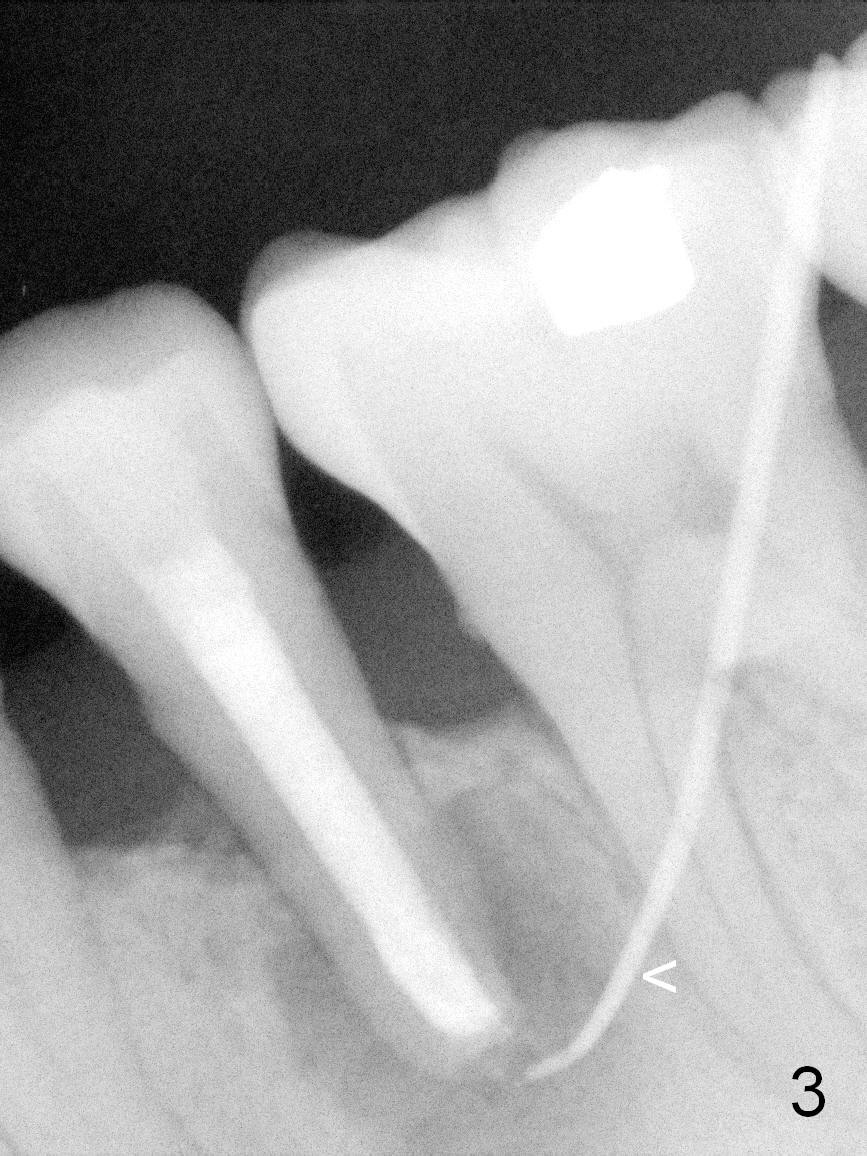

A 45-year-old man (JT) has endo failure at #20 with fenestration (Fig.1,2 black >) and fistula (white <). Insertion of a Gutta Percha at the fistula (Fig. 3 <; PA taken 2 years ago) indicates that the infection is dervied from the apex of the tooth #20. The socket will be soaked with 2% Xylo, 1:50,000 Epinephrine gauze. A 4.5x17 mm tissue-level (Fig.4) or 14 mm bone-level implant is placed as lingual as possible (Fig.5 green). If primary stability is achieved, an abutment is placed (pink). A large piece of resorbable membrane is used to cover the buccal defect (including buccal recession, fenestration and fistula (Fig.6 yellow dashed line). Two small pieces of non-resorbable membrane are placed to cover the gingival recession and the fenestration (Fig.7 white dashed line, buried underneath the edge of the gigniva). Then place bone graft buccally. Place a small piece of gauze (one layer) or plastic (from Tatum implant bag) over the 2nd membrane over the gingival recession and fabricate an immediate provisional. When the acrylic is partially set, remove the gauze or plastic from the provisional. After trimming and polishing, the provisional is cemented to securely keep the 2nd membrane in place. When the wound is healing and the 2nd membrane is stable, trim the buccal extension of the provisional. It is expected that the buccal hard and soft tissue will regenerate over the implant.